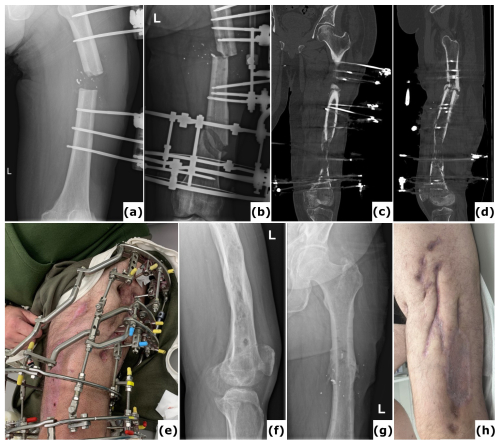

Figure 2Fracture-related infection (FRI) of the tibia. An 18-year-old patient presented with a Gustilo-Anderson type III open fracture of the tibia and fibula. (a) Anteroposterior radiograph demonstrates a comminuted fracture of both the tibia and the fibula. (b) The anteroposterior radiograph indicates fixation of the fracture using an intramedullary nail. The defect was managed with MIMT. (c) Six months post-injury, the patient was referred with multiple fistulas, confirming FRI. (d–e) Anteroposterior radiograph and computed tomography (CT) images were taken after the revision procedure. Removal of the implant and thorough surgical debridement resulted in a large segmental bone defect. The images show the progression of bone transport over a 10 mm intramedullary nail. White arrows point to the off-label locking hole created during the procedure. Once bone transport is complete, the segment can be secured with a 4 mm interlocking screw and the frame can be removed, which reduces the external fixation time.

Figure 3Bone transport utilizing external fixation. A 51-year-old patient presented with a Gustilo-Anderson type II open fracture of the distal tibia and fibula. (a) Clinical presentation upon admission to the emergency department, illustrating the open fracture. (b–c) Computed tomography (CT) images obtained at the time of referral, 3 months after initial stabilization with a standard external fixator, reveal absence of bone healing and significant destruction of the tibiotalar joint. (d–e) Anteroposterior radiographs demonstrate ongoing bone transport using a conventional ring fixator. Intraoperative cultures were negative. Note: Due to severe peripheral artery disease, there was a high risk of amputation; consequently, the corticotomy was performed at a lower level than the standard metaphyseal site. (f–i) CT scans, as well as anteroposterior and lateral radiographs, confirm complete consolidation at all sites at 2 years post-procedure. (j) Clinical evaluation at 2 years showed no signs of infection, and the patient was able to ambulate independently.

Figure 4Chronic infection (osteomyelitis) following extended external fixation. (a) Clinical image presenting a fistula with purulent fluid drainage in a 64-year-old patient after multiple surgical procedures for fracture-related infection (FRI) of the proximal tibia with non-union. (b) Anteroposterior radiograph of the tibia showing consolidation of the proximal tibia fracture; the external fixation time (EFT) was 16 months. (c) Clinical image depicting a chronic wound on the posterior aspect of the ankle in a 54-year-old patient after several surgical interventions for FRI of the distal tibia. Bone transport was performed as treatment, with an EFT of 12 months. At referral, the patient had local and systemic signs of infection and was prescribed oral antibiotics. These episodes have recurred intermittently over 3 years following removal of the external fixator. (d) Anteroposterior radiograph of the tibia demonstrating consolidation at all sites.